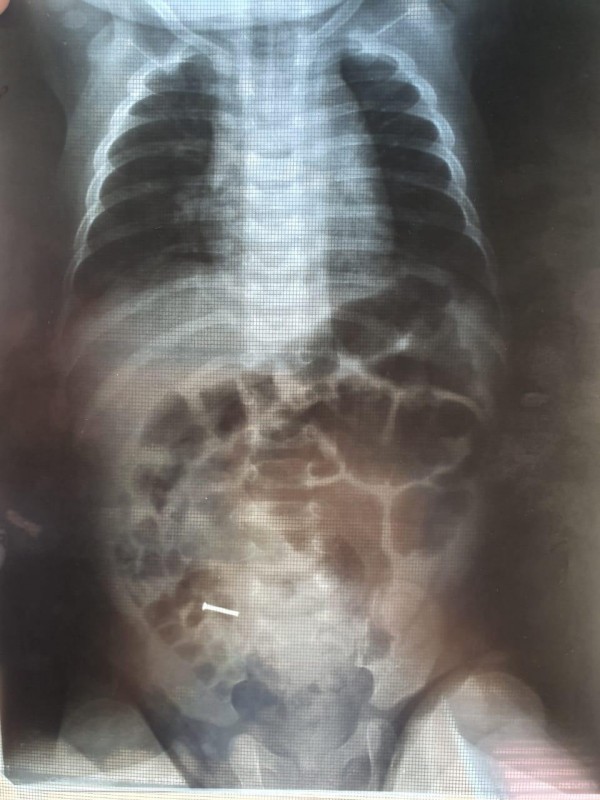

Врачи Шымкента спасли четырехмесячного ребенка, который проглотил гвоздь, передает Tengrinews.kz со ссылкой на Управление здравоохранения города.

По словам родителей малыша, ребенок играл с гвоздем и случайно его проглотил. Родители этого не заметили, и только при медицинском обследовании в желудке малыша было выявлено инородное тело.

"Родители ребенка изначально обратились к врачам шымкентской городской клинической больницы по поводу того, что у малыша болели суставы. Специалисты-ортопеды при рентгене случайно обнаружили в желудочно-кишечном тракте ребенка железо, и ему была оперативно проведена операция, ведь над малышом нависла реальная угроза: гвоздь мог проколоть внутренние органы. Операцию провели квалифицированные врачи из городской детской больницы: Султангали Сарыбай, Амантаев Жаксылык, Курманалиев Асанбай. Во время операции хирурги смогли точно обнаружить инородное тело и извлечь его из желудка", - говорится в официальном сообщении.

После проведенной закрытой операции состояние ребенка улучшилось, он провел в больнице около недели и был выписан домой. Сейчас здоровью малыша ничто не угрожает.